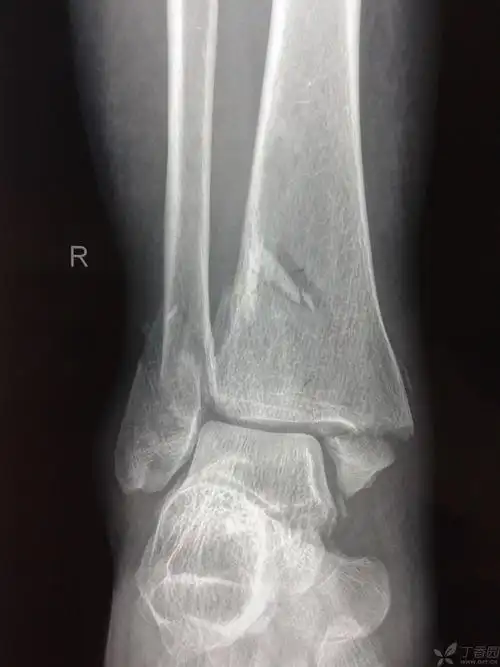

踝关节骨折治疗选择